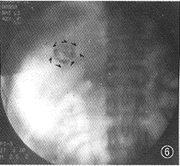

图6例3。 L-TAE术后即时X线摄片显示大小瘤灶内碘油沉积完全,大瘤灶周围充盈碘油的引流静脉近端闭塞(

),图5见到的早显胆囊静脉等未再显现

3.本组病例并发的AVS L-TAE术后摄片所见:并发AVS的22例CHL中,21例在L-TAE术后即时行X线摄片发现:碘油混合剂通过未完全闭塞的AVS再充盈于少部分门静脉周围支或引流静脉者11例(图2,4);DSA显现的AVS完全闭塞而未见任何静脉充盈碘油混合剂者10例(图6),但其中1例(AHVS)于L-TAE术后3个月DSA复查又见少部分肝静脉支早显(图9);所有21例CHL的血管湖内皆见到碘油混合剂的较完全或完全沉积(图2,4,6)。